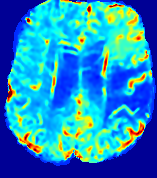

Slice #1Slice #2Slice #3Slice #4Slice #5Slice #6Dgtsuperscript𝐷gtD^{\text{gt}}Refer to captionRefer to captionRefer to captionRefer to captionRefer to captionRefer to caption(a)Refer to captionRefer to captionRefer to captionRefer to captionRefer to captionRefer to caption(b)Refer to captionRefer to captionRefer to captionRefer to captionRefer to captionRefer to caption(c)Refer to captionRefer to captionRefer to captionRefer to captionRefer to captionRefer to caption(d)Refer to captionRefer to captionRefer to captionRefer to captionRefer to captionRefer to caption(e)Refer to captionRefer to captionRefer to captionRefer to captionRefer to captionRefer to caption(f)Refer to captionRefer to captionRefer to captionRefer to captionRefer to captionRefer to captionRefer to caption000.060.060.060.120.120.120.180.180.180.240.240.240.300.300.30(mm2/s)𝑚superscript𝑚2𝑠(mm^{2}/s)

Figure 13: PIANO effectiveness and robustness testing: diffusion imaging via diffusion. Top row shows Dgtsuperscript𝐷gtD^{\text{gt}} used for simulating the ground truth pure diffusion. (a)-(f) refer to the results for D𝐷D estimated from the ground truth pure diffusion image time-series where Rician noise at levels 0%, 2%, 4%, 6%, 8%, 10% was added respectively.

Note this is likely not a spatially representative ground-truth for perfusion imaging, as it measures different effects from diffusion imaging. However, we still use it as a quasi-realistic pattern of diffusivity in the brain. We also added 2%, 4%, 6%, 8%, 10% levels of Rician noise to obtain simulations of ‘Diffusion Imaging’. The estimated Destsuperscript𝐷estD^{\text{est}} given concentrations of all noise levels for one patient are shown in Fig. 13, PIANO estimation results for all patients are summarized in Fig. 11 (b). Again, PIANO demonstrates its capability to recover the underlying diffusion field. In Fig. 13, when the noise level is increasing, some noisy patterns indeed appear in the associated Destsuperscript𝐷estD^{\text{est}}. Note that the ground truth diffusivity applied in this simulation experiment is about ten times larger than the diffusivity estimated in reality (Fig. 3, Fig. 4).